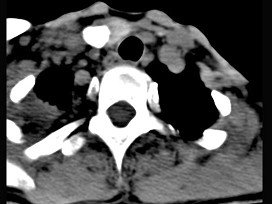

5.男性,40歲,頸部出現(xiàn)無(wú)痛性囊性包塊2年余,CT掃描如圖所示,最可能診斷為  (    )

正確答案:A